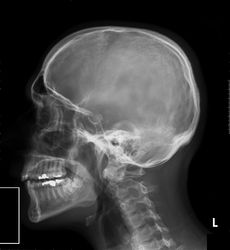

Poté, co Röntgen objevil využití pro pozorování kostních struktur, se rozvinulo jeho užívání v lékařském snímkování. Rentgenové záření může být využito pro zobrazení detailů kostí a zubů (skiagrafie), popřípadě za pomoci vhodných technik i ke zkoumání měkké tkáně (denzitografie, subtrakční skiagrafie, tomografie). Radiologie je specializovaný obor lékařství využívající rentgenového záření v diagnostice. Toto je pravděpodobně nejčastější využití rentgenového záření.